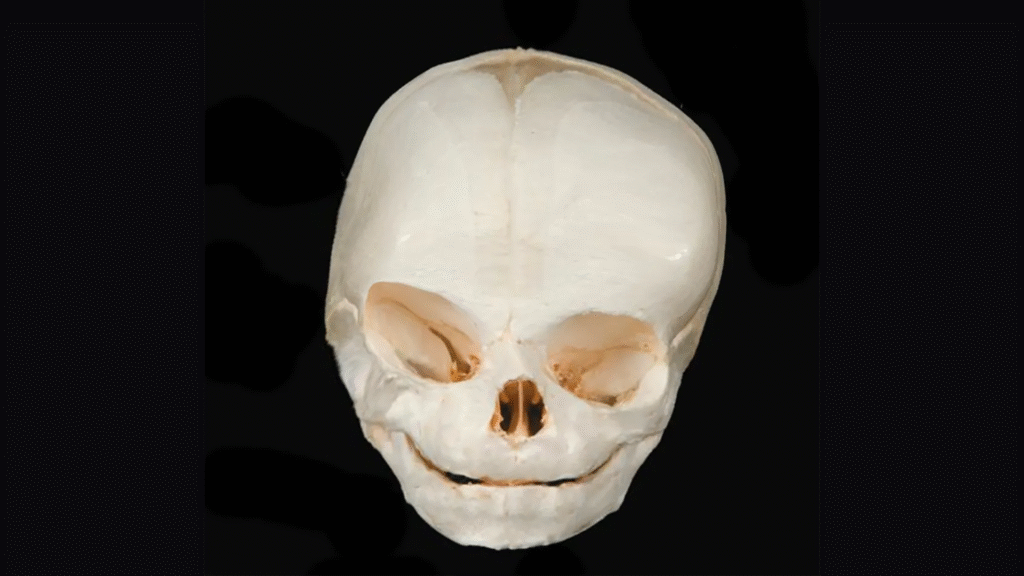

At El Paso Craniofacial Team, the primary treatment for craniosynostosis is surgery. First performed in the late 1800s, surgical approaches have continued to evolve and improve. The two main approaches are Calvarial Vault Remodel (CVR) and endoscopic-assisted surgery, with each tailored to the child’s age, the affected suture, and the severity of the condition.